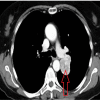

Figure 2

Figure 2. Heterogeneous mass arising from the pleura adjacent to the superior and medial left pulmonary artery